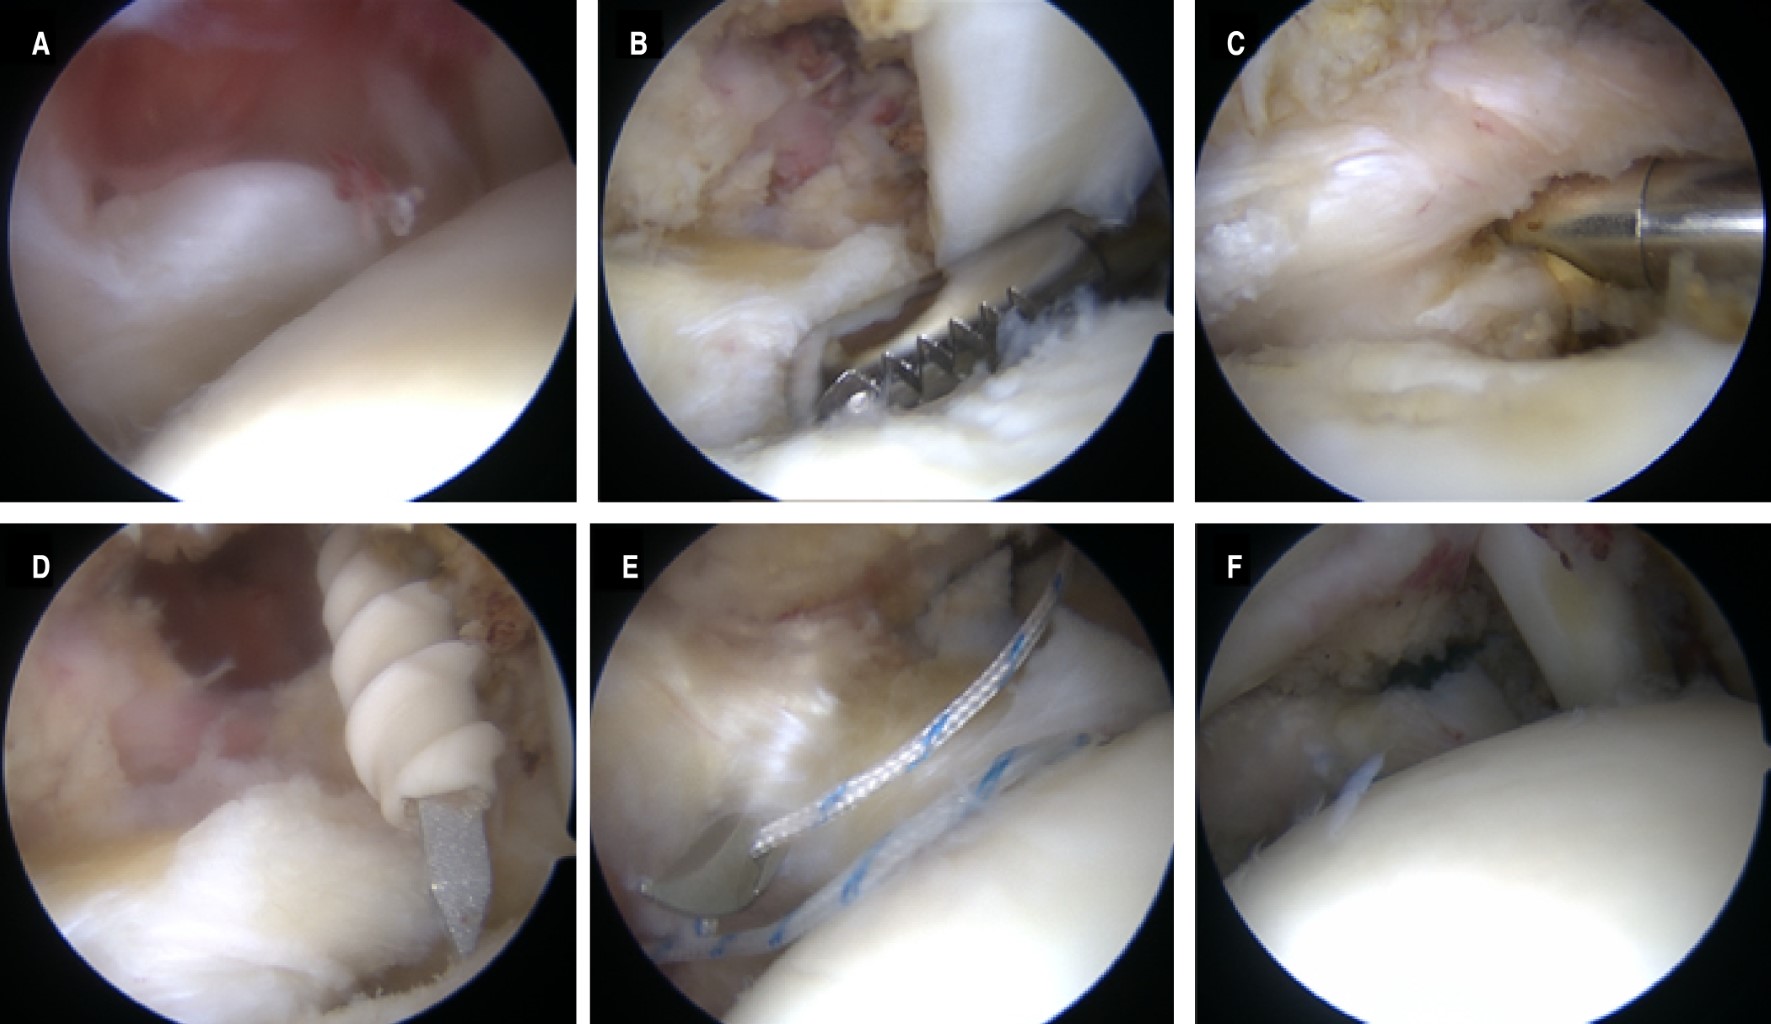

La posición preferida por los autores, silla de playa. Generalmente se utilizan portal posterior, anterosuperolateral (ASP), anteroinferomedial (AIM) y lateral (L). Al momento de realizar la artroscopia diagnóstica se identifica y clasifica la rotura del subescapular con visión desde el portal posterior, se realiza desbridamiento del tejido libre y cicatrizal alrededor del tendón, mientras se expone desde la línea articular de la tuberosidad menor del húmero. En las rupturas grado II y III se libera parcialmente el ligamento glenohumeral medio, y en todos los casos se abre y reseca el intervalo rotador.

A través del portal ASL, se explora y libera el espacio coraco-humeral. Utilizando pinzas se valora la reducción del tendón a su sitio de inserción asistido por el portal L, en caso necesario se realiza liberación del tendón en cuatro superficies del mismo (articular, extraarticular, inferior y superior), como se ilustra en la Figura 3A-C hasta obtener reducción sin tensión.

Se colocan anclas (ya sea bioabsorbible o de sólo sutura) (de una a tres, dependiendo el tipo de ruptura) a través del portal AIM, ayudado por ligera rotación interna, flexión y abducción de 30 grados. Se colocan dos cánulas en los portales anteriores y asistido por el portal L se realiza tracción del tendón y a través del portal ASP. Con ayuda de un instrumento de pasador de suturas (de preferencia una pinza), se realizan puntos de colchonero con cada una de las suturas de cada ancla atravesando el tendón, de tal manera que los nudos permanezcan en la porción extraarticular y buscando una reducción anatómica del mismo, como se ejemplifica en la Figura 3D y E .

Se realizan nudos de afrontamiento para reinserción del tendón, previa decorticación ósea y microperforaciones para estimular la cicatrización biológica.

Es preferible la reducción del tendón en el aspecto intermedio entre la línea articular y el borde superolateral de la tuberosidad menor, como se ilustra en la Figura 3F.

Se recomienda verificar el brazo de palanca del tendón posterior a la reparación y vigilar la tensión del mismo, así como el contacto completo con la superficie ósea.